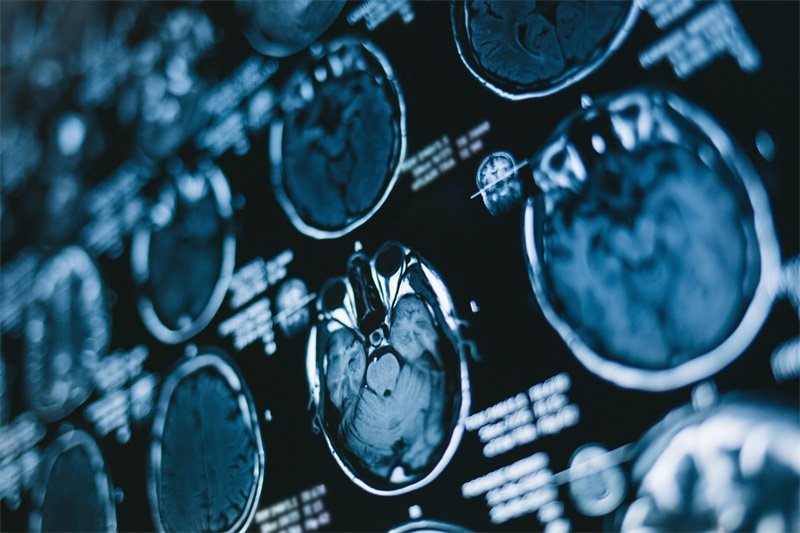

为了确诊蝶鞍区占位灶,医生通常会采用多种诊断手段,包括影像学检查和临床评估。

磁共振成像(MRI)被广泛应用于检测蝶鞍区的结构异常。这种影像学检查清晰度高,能够准确显示肿瘤或囊肿的位置与大小。通过详细分析影像,医生能为患者制定合适的治疗方案。

CT扫描可以提供骨组织的细节,对于评估骨质的侵蚀或改变很有帮助。此外,临床的内分泌评估也是必要的,通过血液测试测量激素水平,了解内分泌功能的情况。